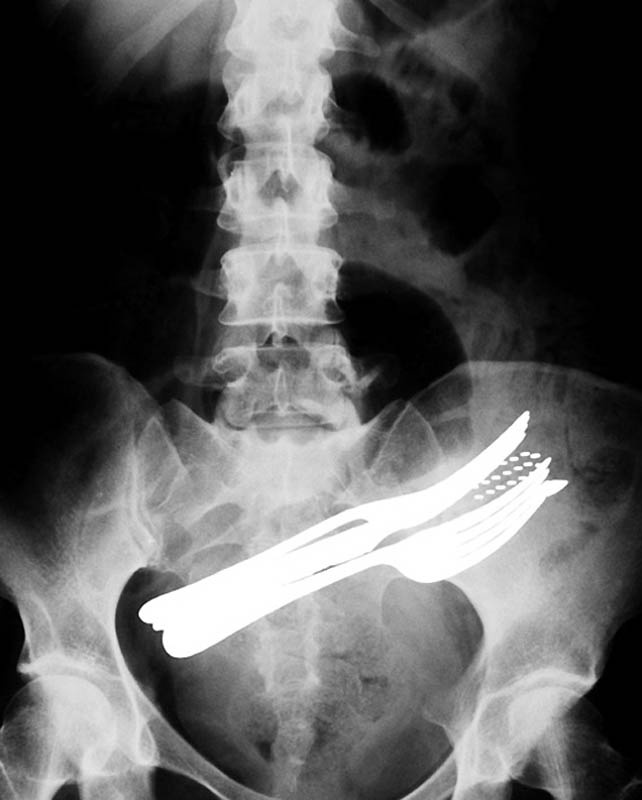

2. Живот пациента, который проглотил две вилки, шариковую ручку и зубную щетку.